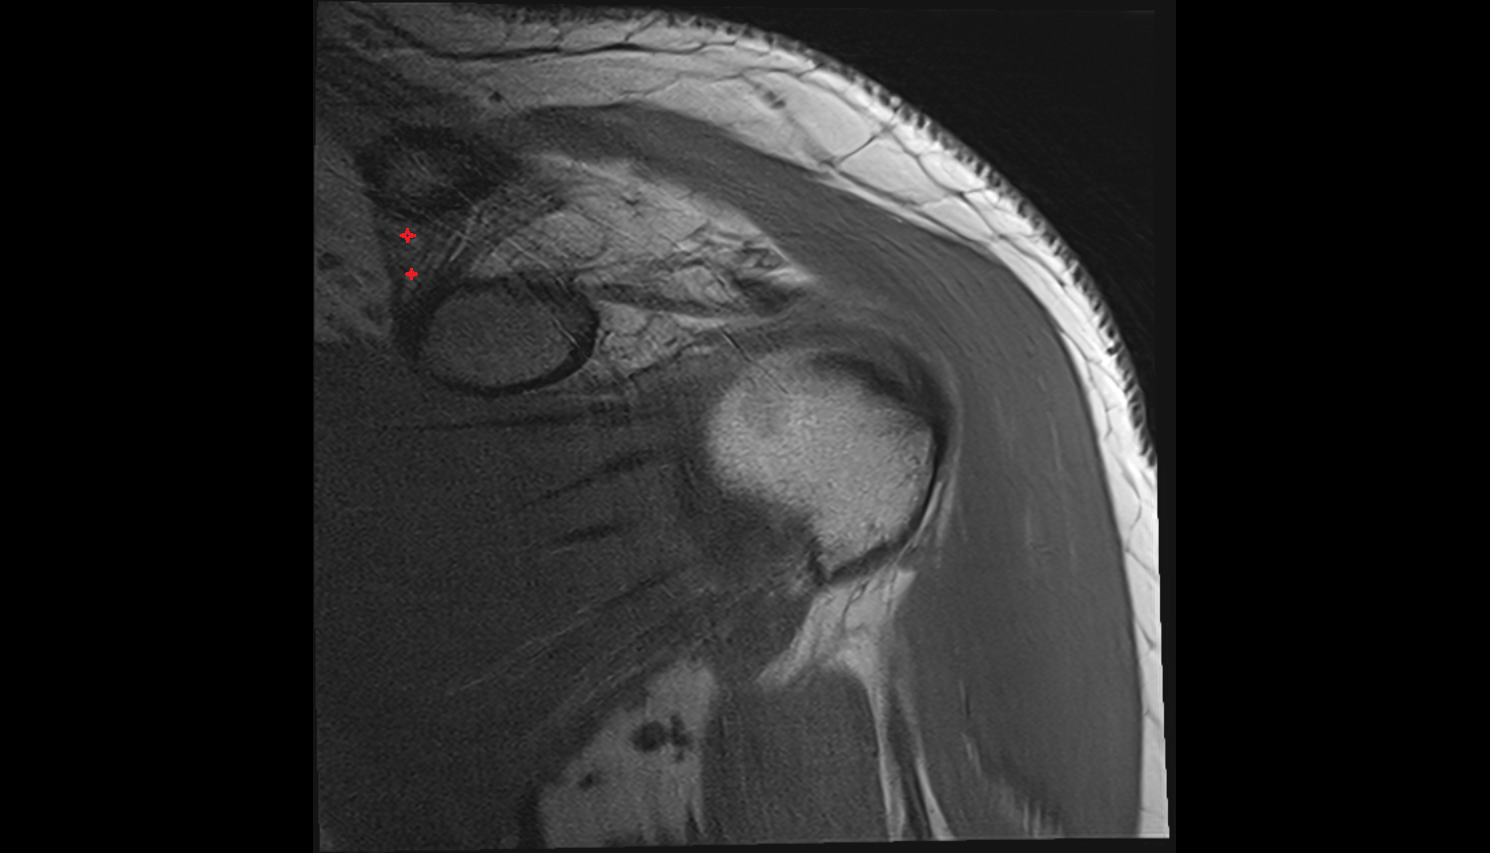

- Supraspinatus tendon

- Subscapularis tendon

- Glenoid labrum

- Glenohumeral joint capsule

- Shoulder joint (glenohumeral joint)

- Glenoid fossa

- Head of humerus